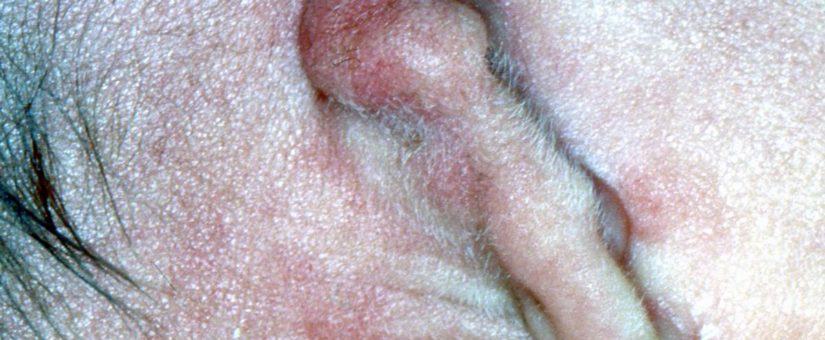

Microtia

I (W. Wertelecki, M.D.) see a hypoplastic malformed ear generally referred to as microtia. Instances as severe as illustrated here most often are associated with atresia or narrowing (stenosis) of the external ear canal. Malformations of the tympanum and middle ear ossicles are common as well as some degree of hearing loss. Please note less severe instance of microtia (there is evidence of a tragus) as well as a gallery of other types of dysmorphic ears.

PERSPECTIVE: Microtia can be unilateral, sporadic and as isolated malformation. However, it is also a feature of several dysmorphic syndromes such as Goldenhar, Treacher-Collins and other syndromes. There are instances of 18q- syndromes associated with external ear canal atresia and the presence of virtually normal pinnae (ear or auricles) – this is provocative because atretic ear canals are strongly associated with atretic pinnae (microtia or anotia.